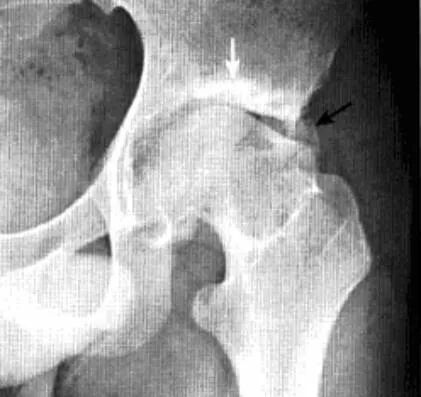

髋关节色素沉着绒毛结节性滑膜炎

一种侵及关节、腱鞘、滑囊或肌腱组织的良性增生伴色素沉着性病变。一般单关节发病,*常累及膝关节,其次是髋关节、踝关节、肩关节、肘关节。

病理:表面凹凸不平,有绒毛状滑膜皱襞覆盖,累及关节囊及周围软组织内血管和神经结构。

临床表现:以20-40岁青年女性多见,多有髋部外伤史,早期无特征,进展缓慢。

影像诊断:早期诊断缺特异性,晚期出现典型骨质破坏。MRI检查具较强特异性及定性诊断作用。